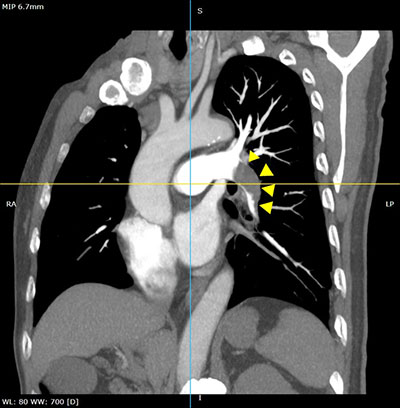

患者前期接受了牙龈癌腓骨取瓣移植术,术后卧床休息,突然出现左下肢明显肿胀,入厕后晕厥,救护车送入医院急救中心。入院时患者胸闷不适,收缩压小于100mmHg,心率增快。医院完善各项检查后进一步明确诊断为左肺大面积肺栓塞、左下肢深静脉血栓形成(混合型)。

左肺大面积肺栓塞

手术采用局麻的方式,经皮穿刺右股静脉,进入肺动脉造影后进一步明确诊断,左肺大面积肺栓塞。将鞘管到达左肺动脉后,应用Tendvia装置给予取栓,取出大量混合性血栓,取栓后左肺动脉血流完全恢复,血流分级达到Grade Ⅰ级,患者胸闷立即缓解。